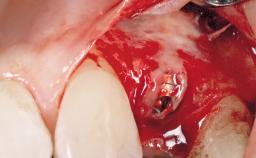

Immediate Placement of an Implant in a Maxillary Left Central Incisor Site

A 33-year-old female patient presented with an upper left central incisor that required extraction after a failed endodontic therapy. The tooth had been traumatized when the patient was a teenager and had undergone several endodontic treatments, including two apicectomy procedures. The patient was in good health and did not smoke. Clinical examination showed that the patient had a high lip line. In full smile, the gingival margins of the upper teeth were visible to the first molars. The gingival margins of central incisors 11 and 21 were only just showing. Examination of tooth 21 confirmed that the tooth was mobile and had hypererupted by 1 mm.

| Placement Protocol | Immediate implant placement |

| Tooth Site | Maxillary incisor or canine |

| Socket Morphology | Single-root socket |

| Socket Integrity | Damage to one or more bone walls |